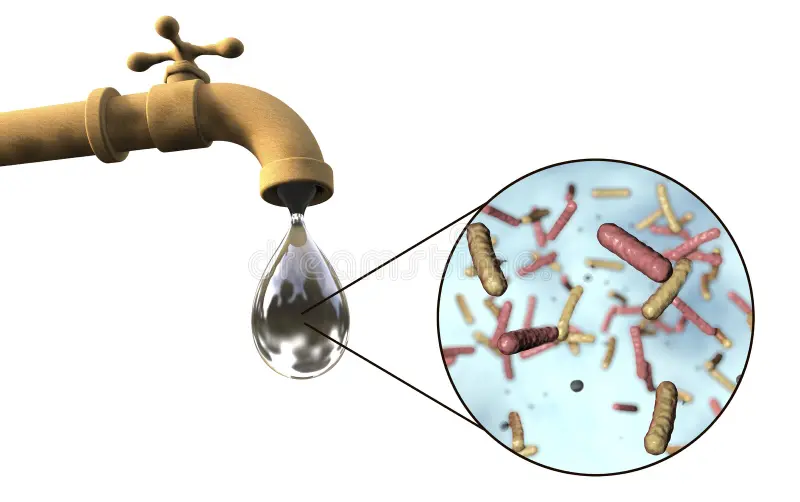

💧 Waterborne Diseases (Hepatitis, Diarrhoea, Cholera)

Floods and poor sanitation increase waterborne diseases like hepatitis A/B/C, cholera, typhoid, and diarrhoea . In addition, contaminated water is a big reason for these outbreaks.

👉 Prevention: always drink boiled or filtered water, wash hands, and avoid eating food from unhygienic places.